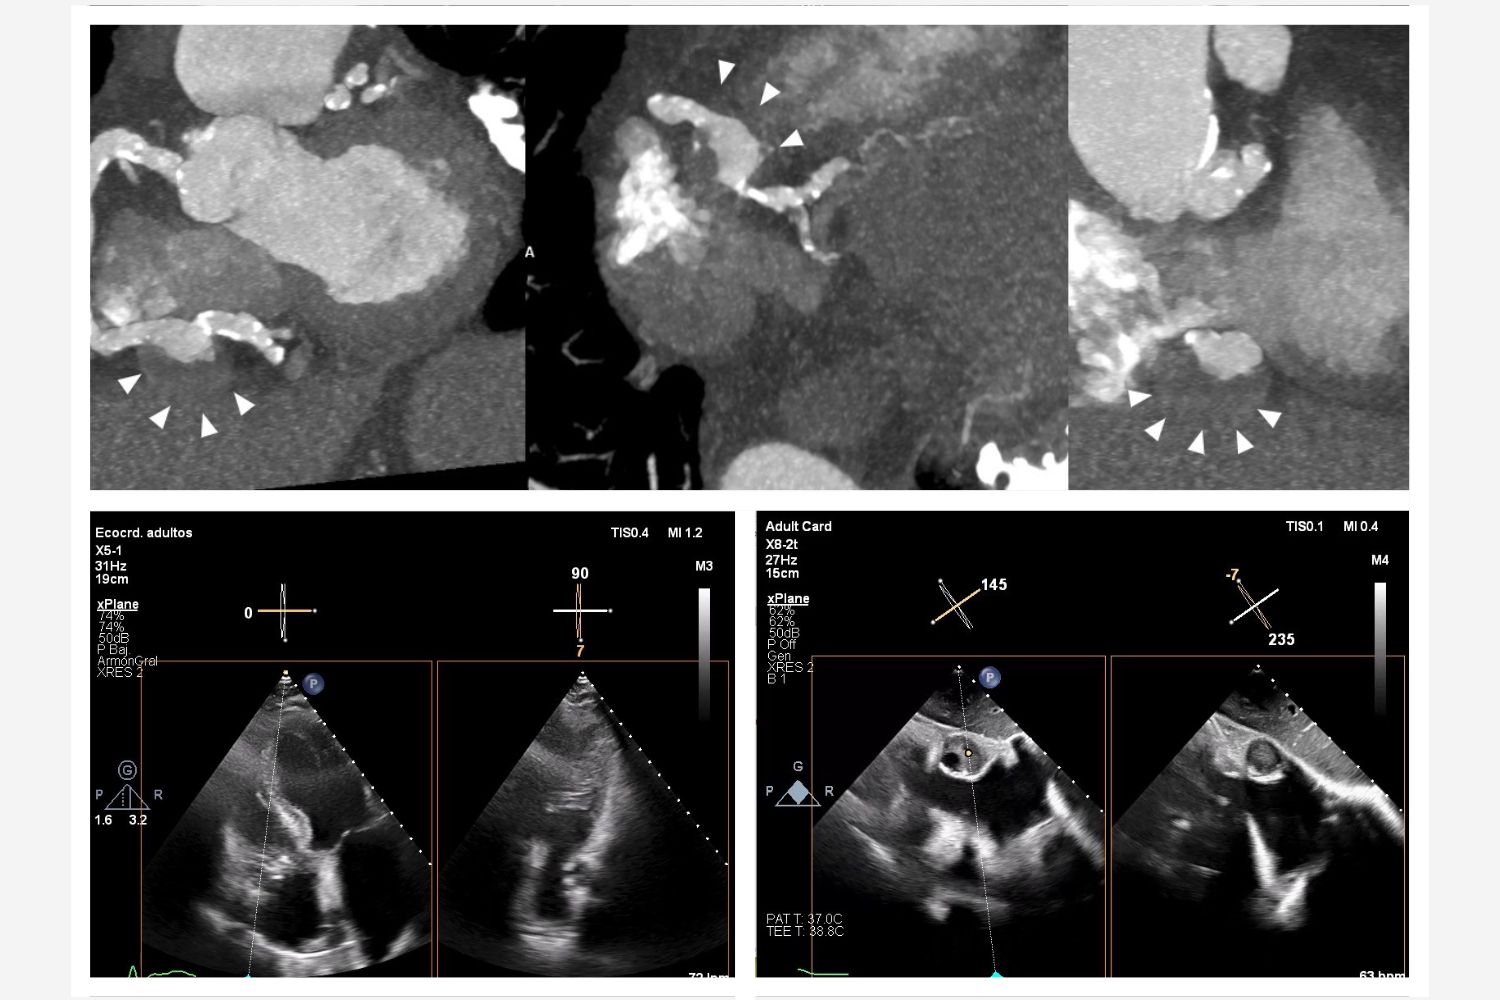

Image of the Week - 14 May 2025

13 May 2025

Image of the week